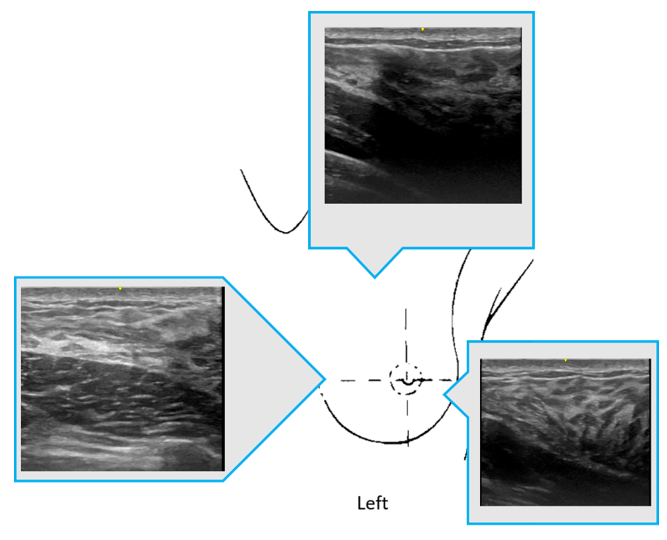

傳統平胸手術主要依賴視覺與觸診來區分乳腺、脂肪及肌肉,而超音波技術可在術前精確分層,不僅提升選擇性腺體切除的準確性,還能在輔助脂肪抽吸手術中幫助定位脂肪分布,進而提高塑形的對稱性。由於皮下脂肪分布不均(如圖所示),術前可先評估胸骨前脂肪厚度作為基準,再與各部位脂肪進行比較,以決定脂肪抽取的範圍與比例。透過這種評估方式,可降低術後皮膚表面不平整的風險。此外,由於乳頭下方脂肪層較薄,術前評估時可考慮適量保留腺體以支撐乳頭位置,避免術後產生中央凹陷的情況。